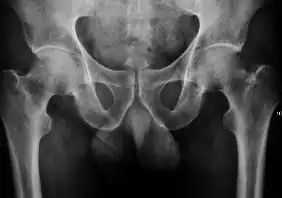

- Joint effusion

-

Figure 2C. AP view of a patient with left hip effusion secondary to trauma showing widening of the medial joint space.[1]